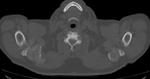

Интереснейший случай был выставлен Татьяной Валентиновной

Наблюдение Татьяны Валентиновны

Первый раз подагрический артрит с таким размахм вижу...

Мне вспомнилось слово мутилирующий.

Изначально подумала на ревматоид, если честно.